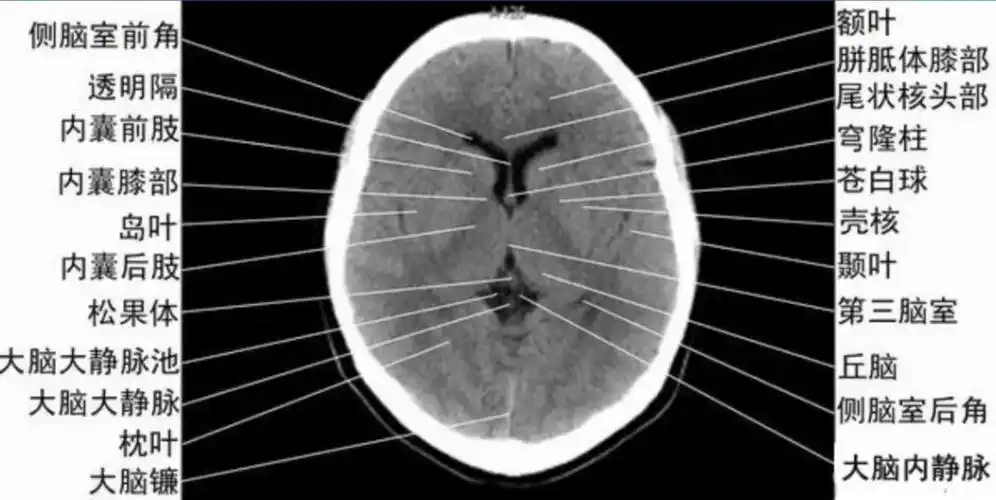

收藏!影像医生必备 | 手把手教你读懂颅脑ct